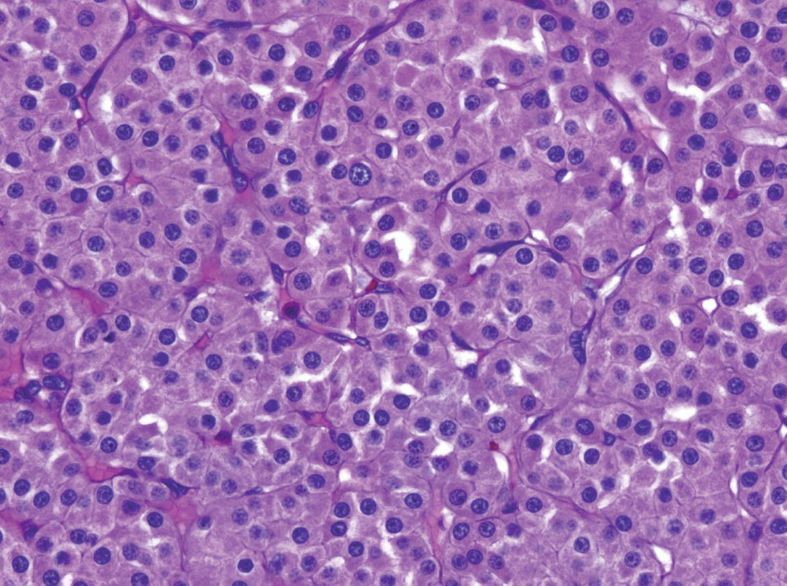

Clear cell renal cell carcinoma

On gross anatomy, clear cell appears as a granular, golden-yellow-orange, well-circumscribed tumor with a color and texture similar to normal adrenal cortex.

The main indicator in all cases is the presence of clear cell aggregates or nests within cyst walls or septae. A net-like array of delicate capillaries is often present.